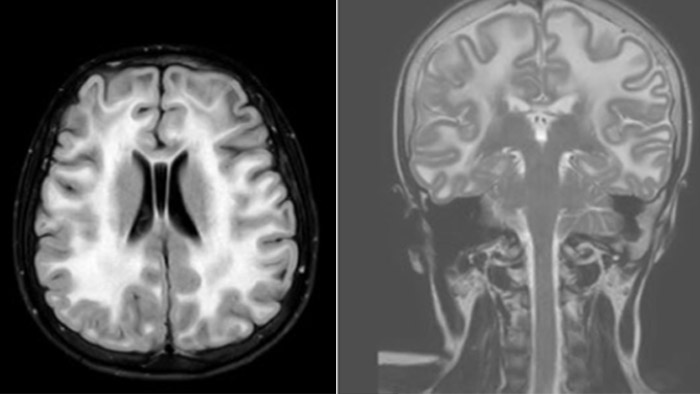

Leukodystrophy in a teenager